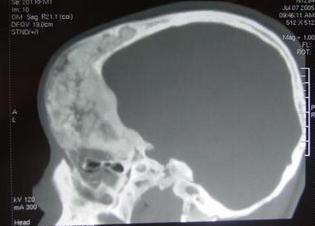

头部对人的重要性不言而喻,头部受伤,也就是颅脑外伤,严重的可能会危及宝宝生命,所以孩子伤到脑袋的时候,家长要特别注意。

人的颅骨主要分为面颅和脑颅两部分,面颅位于人的面部,而脑颅位于颅的后上部,包括顶骨和 颞骨等部位,和面颅一同围成颅腔来容纳脑,保护人的大脑。

而后脑勺没有颅骨的保护,则相对脆弱,而且受伤之后当时的表现不明显,不能准确判断是否有问题。如果孩子是后脑勺着地,或者是后脑勺遭到撞击,那后果常常会更加严重,比如颅内出血,要尽快带孩子去医院。